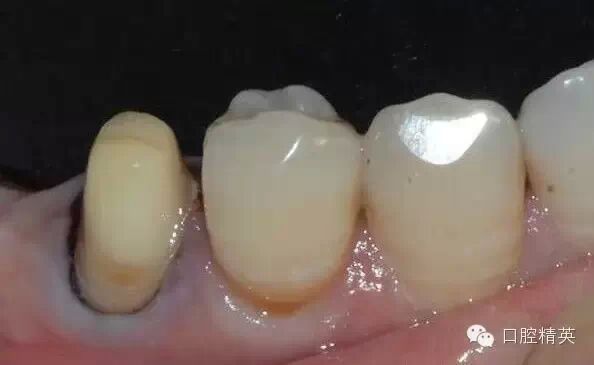

頰面和鄰面的制備

簡單制備完成后,檢查咬合的距離